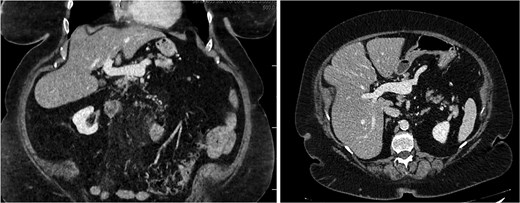

A 76-year-old female with a 3-day history of left upper abdominal pain, vomiting, and haematochezia. Her history included pulmonary embolism, multiple deep vein thromboses, with no ongoing anticoagulation, and an open partial colectomy for complicated diverticulitis a decade earlier. On admission, she was afebrile but tachycardic and showed localized tenderness in the left hypochondrium. Laboratory revealed leucocytosis with a white blood cell count (WBC) of 12 G/L, elevated C-reactive protein (CRP) of 46 mg/L, and hyperlactatemia of 2.6 mmol/l. Enhanced computed tomography (E-CT) revealed jejunal venous ischemia in the left upper quadrant, secondary to extensive porto-mesenteric thrombosis with reduced bowel wall enhancement, distention, and free intraperitoneal fluid (Fig. 1). She was managed conservatively with unfractionated heparin (UFH) with a bolus of 5000 U/l followed by 30 000 U/l/24 h (target INR 0.35–0.7), Piperacillin-Tazobactam, and bowel rest. After 48 h of monitoring in the intensive care unit (ICU), she exhibited marked biological and clinical improvement. E-CT on the third day showed restored bowel wall enhancement and stable porto-mesenteric thrombosis (Fig. 2). She was discharged on therapeutic low molecular weight heparin (LMWH) with enoxaparin sodium 120 mg every 12 h. At the 3-month follow-up, E-CT revealed near-complete thrombus resolution, without intestinal sequelae (Fig. 3).

Three-month E-CT of the first patient showing nearly complete thrombosis resolution, with no signs of intestinal distress.